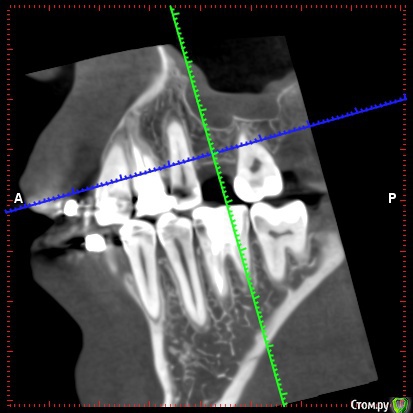

Bors Опубликовано 1 декабря, 2019 Автор Поделиться Опубликовано 1 декабря, 2019 по высоте хватает, ширину нужно смотреть на Кт (качать весь архив не буду) покажите срезы областей интересаСрезы сам не делал, так как не знаю насколько правильными они будут. Прикрепляю то, что получилось. как правило не влияетЯсно. Просто частенько проскакивает в описаниях тех или иных моделей информация о том, что это идеальный вариант при недостатке костной ткани и т.п. Не совсем понятно стоит ли переплачивать за тот же Nobel или выбрать что-то дешевле. Хочется поставить и забыть на всю жизнь про этот зуб. Ссылка на комментарий

red_butler Опубликовано 1 декабря, 2019 Поделиться Опубликовано 1 декабря, 2019 костная пластика не нужна, разве что небольшой закрытый синуслифтинг слева Ссылка на комментарий

Irouil Опубликовано 3 декабря, 2019 Поделиться Опубликовано 3 декабря, 2019 Что касается синус-лифтинга, то по 26-му зубу мне сообщили, что он действительно не нужен, а вот по 16-му что-то вроде пограничного положения. Все наоборот. Но синус лифт там требуется минимальный. Астра тёк прекрасные имплантаты Ссылка на комментарий